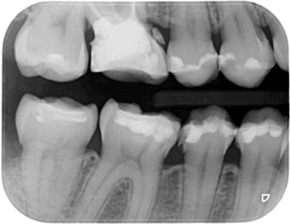

Дигиталните зъбни снимки са подредени в хронологичен ред. При влизане в досието на пациент се виждат всички негови дигитални зъбни снимки, направени във времето, което дава възможност да се проследи развитието на лечението.